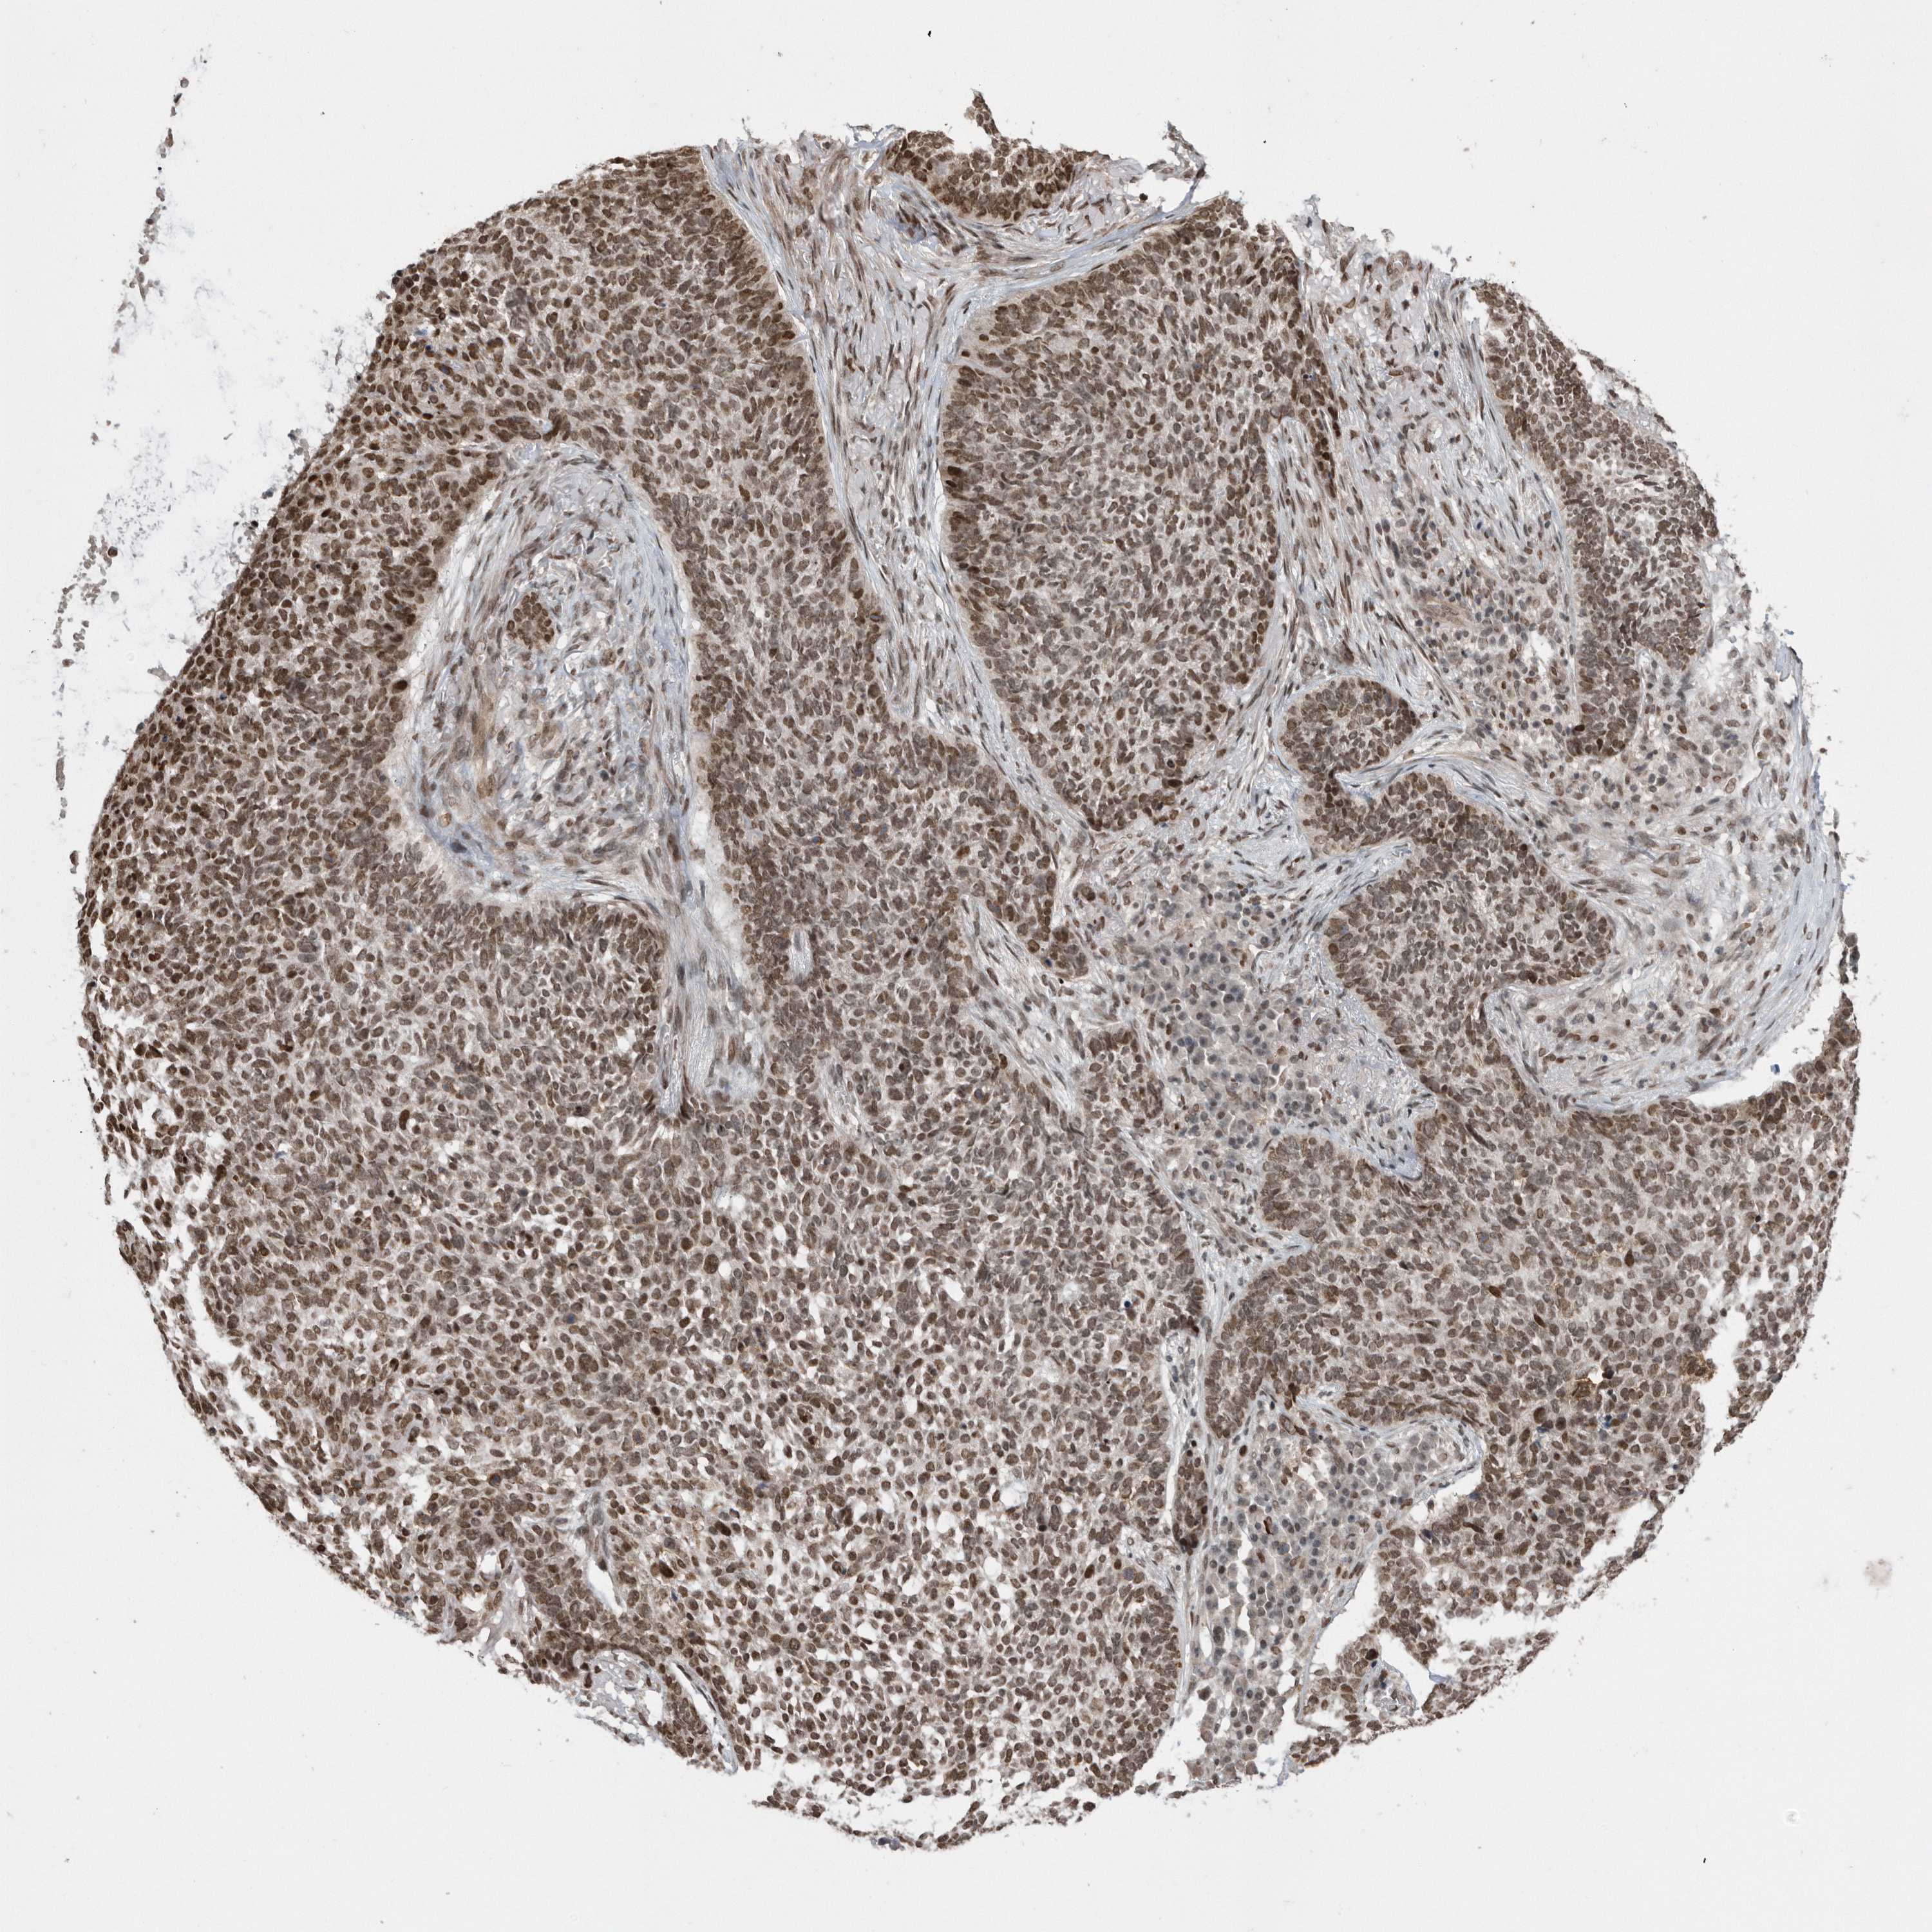

Basal cell and squamous cell cancer

SKIN CANCER - Protein expressioni

A mouse-over function shows sample information and annotation data. Click on an image to view it in a full screen mode. Samples can be filtered based on level of antibody staining by selecting one or several of the following categories: high, medium, low and not detected. The assay and annotation is described here.

Antibody stainingi

Antibody staining in the annotated cell types in the current human tissue is reported as not detected, low, medium, or high, based on conventional immunohistochemistry profiling in selected tissues. This score is based on the combination of the staining intensity and fraction of stained cells.

Each image is clickable and will lead to virtual microscopy that enables deeper exploration of all samples and also displays staining intensity scores, fraction scores and subcellular localization as well as patient and tissue information for each sample.

Antibody CAB034925

Staining

High

Intensity

Strong

Quantity

>75%

Location

Nuclear

Squamous cell carcinoma, metastatic, NOS